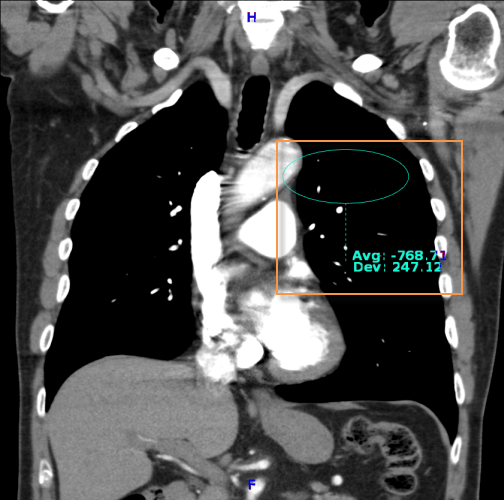

The Hounsfield annotation tool creates a region of interest and calculates its average pixel value and the standard deviation on the distribution.

To obtain a Houndsfield Value measurement:

Select the

Hounsfield Value  icon

icon

Click on the region of interest

Drag on the mouse to encircle the area

Release the mouse button

The default region of interest drawn on the image is a true circle. When resizing the ROI, maintain a true circle by using the corner grab points

The center grab point  will move ROI around the image and others will elongate

or narrow.

will move ROI around the image and others will elongate

or narrow.